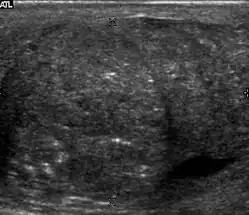

Sonography of a normal testis. The normal testis presents as a structure having homogeneous, medium level, granular echotexture. The mediastinum testis appears as the hyperechoic region located at the periphery of the testis as seen in this figure.

The normal adult testis is an ovoid structure measuring 3 cm in anterior-posterior dimension, 2–4 cm in width, and 3–5 cm in length. The weight of each testis normally ranges from 12.5 to 19 g. Both the sizes and weights of the testes normally decrease with age. At ultrasound, the normal testis has a homogeneous, medium-level, granular echotexture. The testicle is surrounded by a dense white fibrous capsule, the tunica albuginea, which is often not visualized in the absence of intrascrotal fluid. However, the tunica is often seen as an echogenic structure where it invaginates into the testis to form the mediastinum testis. In the testis, the seminiferous tubules converge to form the rete testes, which is located in the mediastinum testis. The rete testis connects to the epididymal head via the efferent ductules. The epididymis is located posterolateral to the testis and measures 6–7 cm in length. At sonography, the epididymis is normally iso- or slightly hyperechoic to the normal testis and its echo texture may be coarser. The head is the largest and most easily identified portion of the epididymis. It is located superolateral to the upper pole of the testicle and is often seen on paramedian views of the testis. The normal epididymal body and tail are smaller and more variable in position.